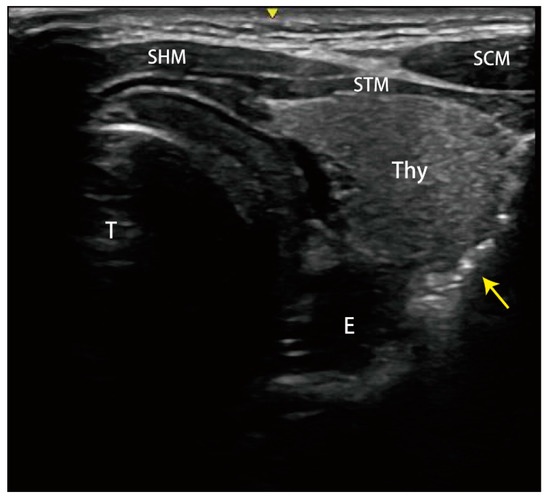

2. Case Presentation